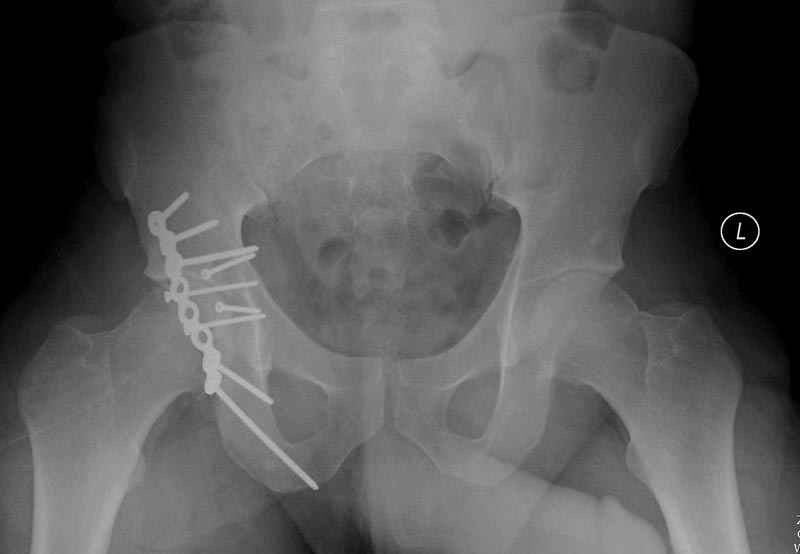

Работаем вместе с хирургами-травматологами (в штатах все травмированные больные поступают, как больные хирургической службы, ортопед выступает в качестве консультанта), т.е. мы даем рекомендации о проведении профилактики тромбоза, совместно решаем о проведении фильтра - вена кава фильтр (см. приложение).

Если вена кава фильтр, хирурги проводят эту процедуру, а медикаментозную профилактику назначаем сами.